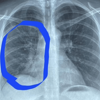

ABD’de Hannah Roth isimli kadın, 4 yıl boyunca elektronik sigara kullandıktan sonra zatürre oldu ve ciğerlerinden şiddetli bir patlama sesi duydu. Ateşi 40 dereceye çıkan Roth, hastaneye kaldırıldı. Röntgenler, 30 yaşındaki Roth'un ciğerlerinin 80 yaşındakininkine benzediğini ortaya çıkardı.

T24’ün aktardığına göre, Roth, "Doktor içeri girdi ve bana röntgenimi gösterdi. Elektronik sigara kullanıp kullanmadığımı sordu. Bu yüzden zatürre oldun dedi. Çantamdaki elektronik sigarayı alıp çöpe attı. Günün her saati içiyordum. Bir anne olarak oldukça korkutucuydu. Bakmam gereken iki çocuğum olduğu için tekrar elektronik sigara kullanamayacağımı biliyorum" dedi.